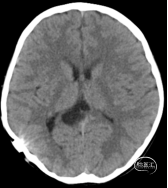

患儿,女性,9岁。因右侧脑室囊肿腹腔分流术后8年余,突发头晕、头痛,呈阵发性,疼痛剧烈,持续数十分钟后缓解。伴视物模糊、恶心、呕吐,就诊当地医院,查颅脑CT提示:右侧脑室囊肿引流术后,脑水肿,侧脑室变小(如下图):

第4日复查颅脑CT平扫提示(如下图)提示:右侧脑室囊肿引流术后,脑水肿较前改善,侧脑室较前略增大。根据患儿目前情况及影像学特点,进一步证实“裂隙脑室综合征”诊断。